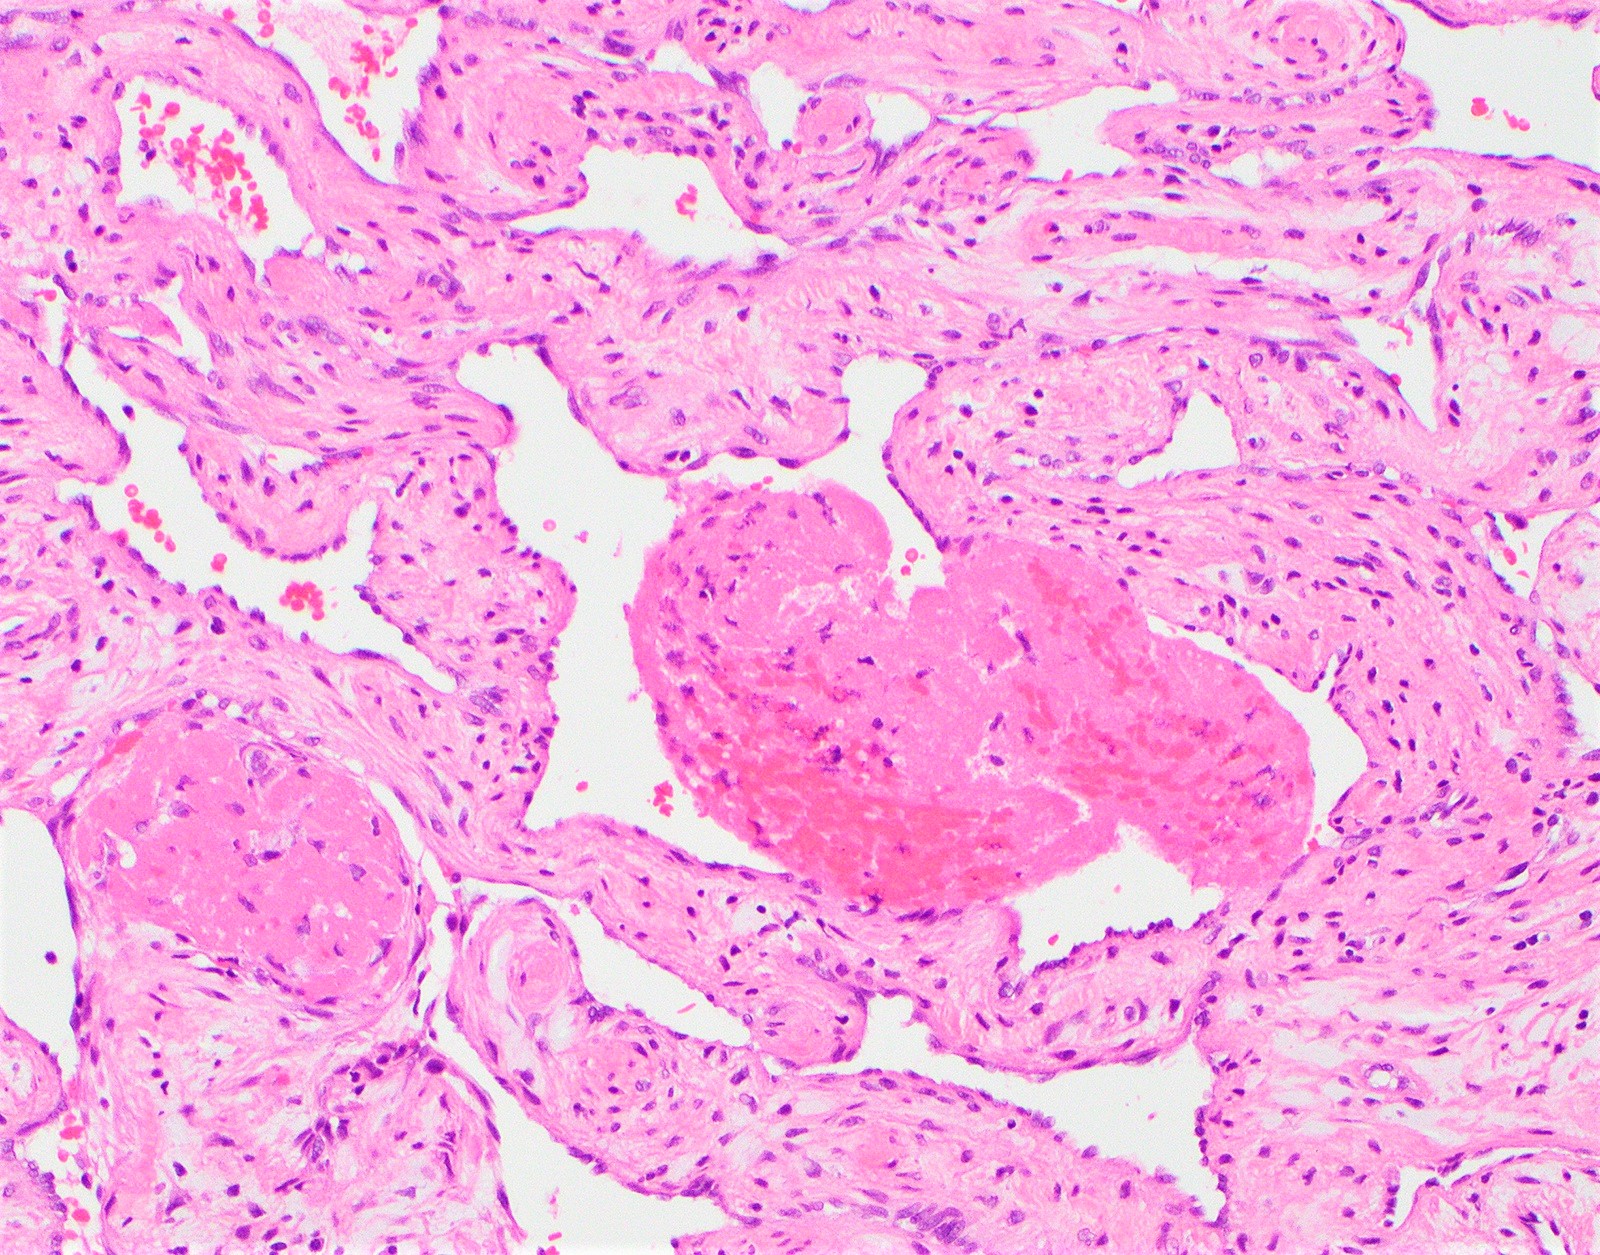

Микропрепараты: Лимфогранулематоз и Нодулярный Склероз

Раздел: Секреты мастерства